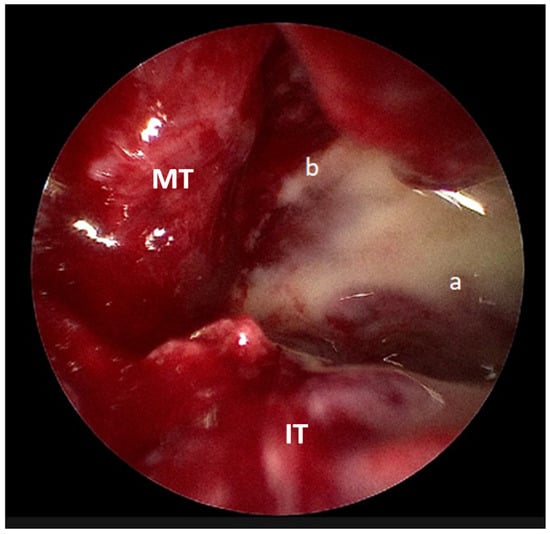

The following day, he underwent endoscopic sinus surgery with drainage of subperiosteal abscess under general anesthesia. Intraoperatively, pus was observed in the left maxillary sinus and subperiosteal area (Figure 4). Postoperatively, his general condition improved; however, tissue and pus cultures obtained from the left maxillary sinus subsequently grew methicillin-resistant Staphylococcus aureus (MRSA). In response, his antibiotic regimen was adjusted to intravenous vancomycin, as recommended by the infectious disease specialist.

Figure 4. Intraoperative endoscopic picture showing pus draining from the (a) maxillary sinus and (b) subperiosteal region (IT: inferior turbinate, MT: middle turbinate).